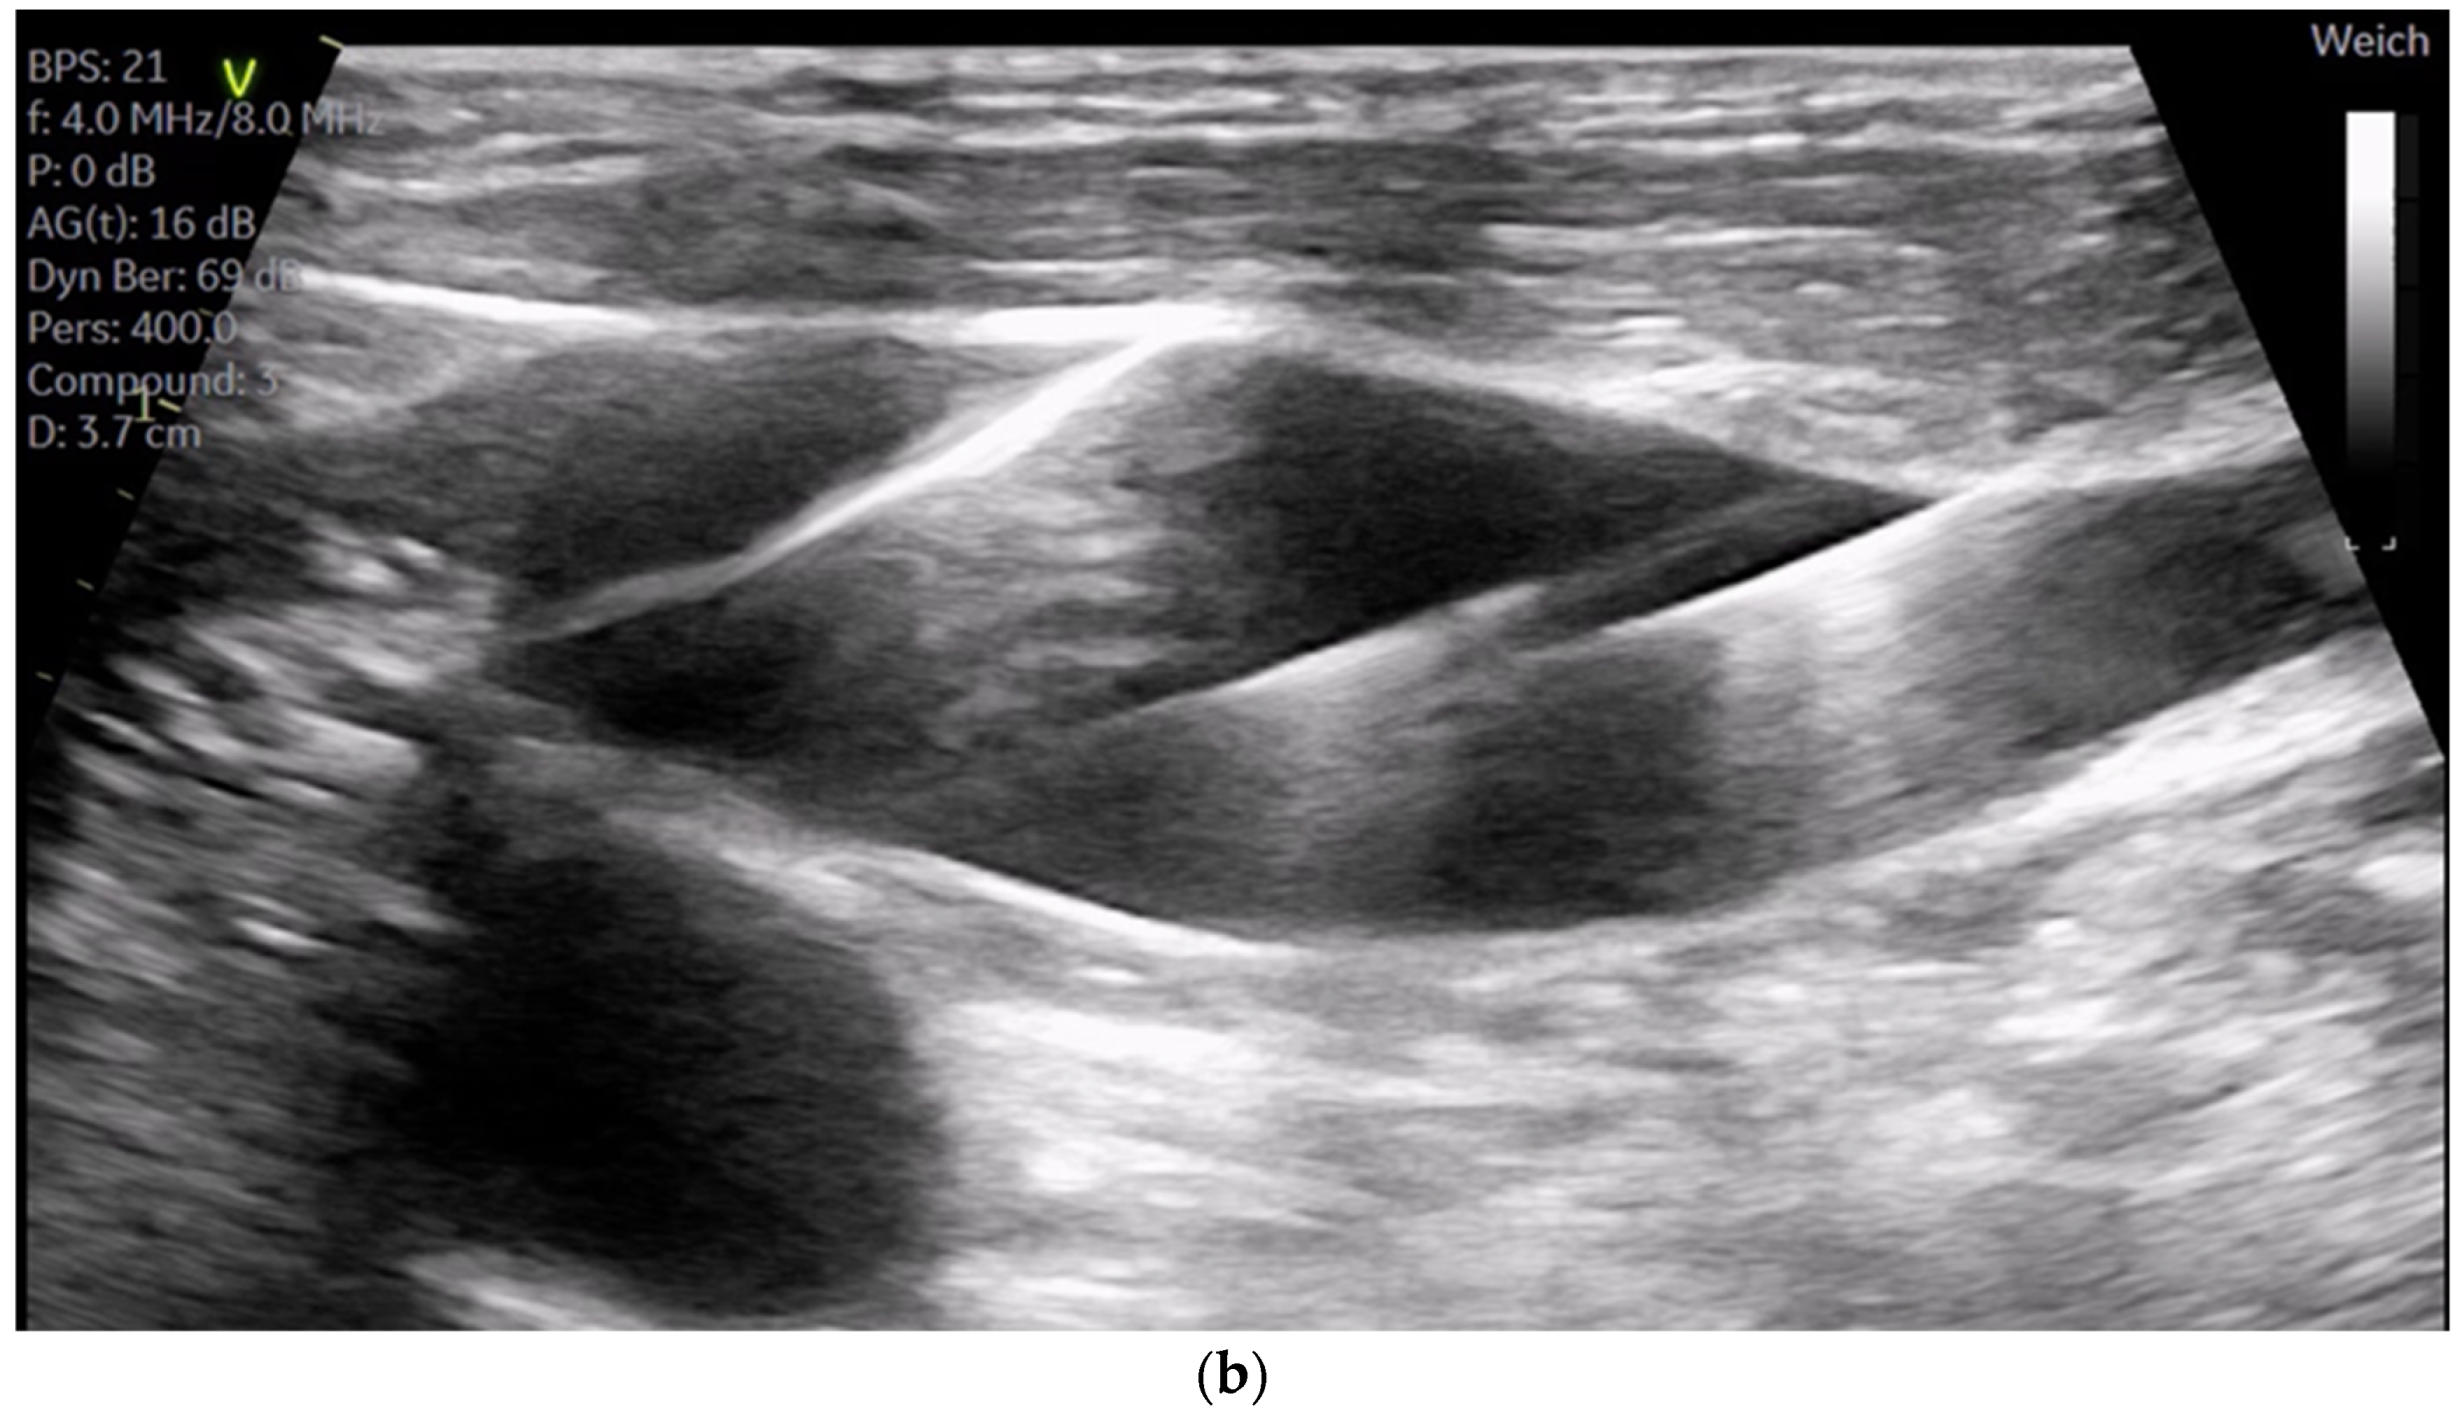

The SVC drainage cannula (Edwards Fr 16/18 OptiSite arterial cannula) is placed via the right jugular vein under ultrasound guidance simultaneously with the central venous catheter insertion. The cannula is positioned caudally to the central venous catheter and other venous lines (see Figure 3a,b). It is important to note that cannulation is performed above the superior thorax aperture to avoid potential complications resulting from intrathoracic vascular damage. We do not perform side-separated cannulation of the central venous catheter and CPB cannula at our center. This approach offers advantages in terms of time management and protection of the contralateral side for possible subsequent punctures during hospitalization. No adverse effects were observed in association with the multiple access procedure.

Figure 3.

(a) shows the catheters inserted in the internal jugular vein right from cranial to caudal as follows: central 4-lumen central venous catheter, 1-lumen 9 FR catheter, and the CPB cannula; (b) shows three guidewires in the right internal jugular vein.